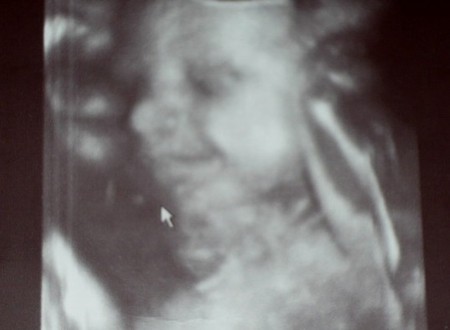

жду девочку, 10 неделя

Сургут

девочки, милые что скажите про Узи?